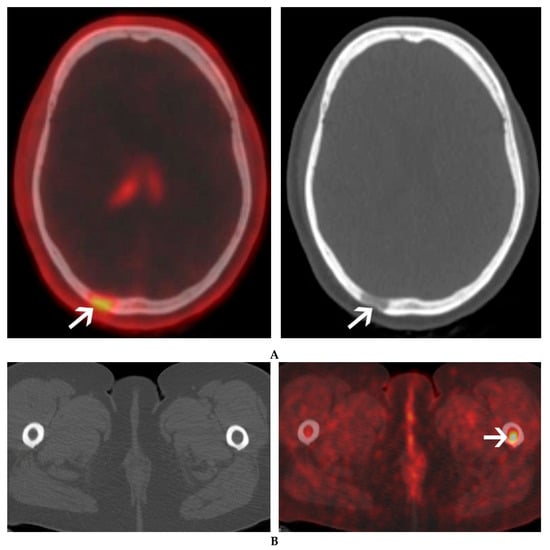

| Areas of impaired detection | -FL of right lower ribs: “liver shadowing” -Liver EMD | Skull FL: “brain shadowing” |